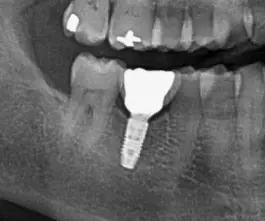

Røntgenbillede viser tandimplantat fastgjort i underkæben

Et tandimplantat er en kunstig tandrod fremstillet af titanium, som indsættes i kæbeknoglen for at erstatte en mistet tand. Implantatet fungerer som en stabil base for en krone, bro eller protese og giver en løsning, der både er funktionel og naturlig i udseendet.

Et implantat består af tre hoveddele:

• Implantatskruen

en titaniumskrue, der indsættes i kæbeknoglen og fungerer som tandroden.

• Abutmentet

en forbindelsesdel, der monteres på implantatskruen og fungerer som overgang mellem implantatet og kronen eller broen.